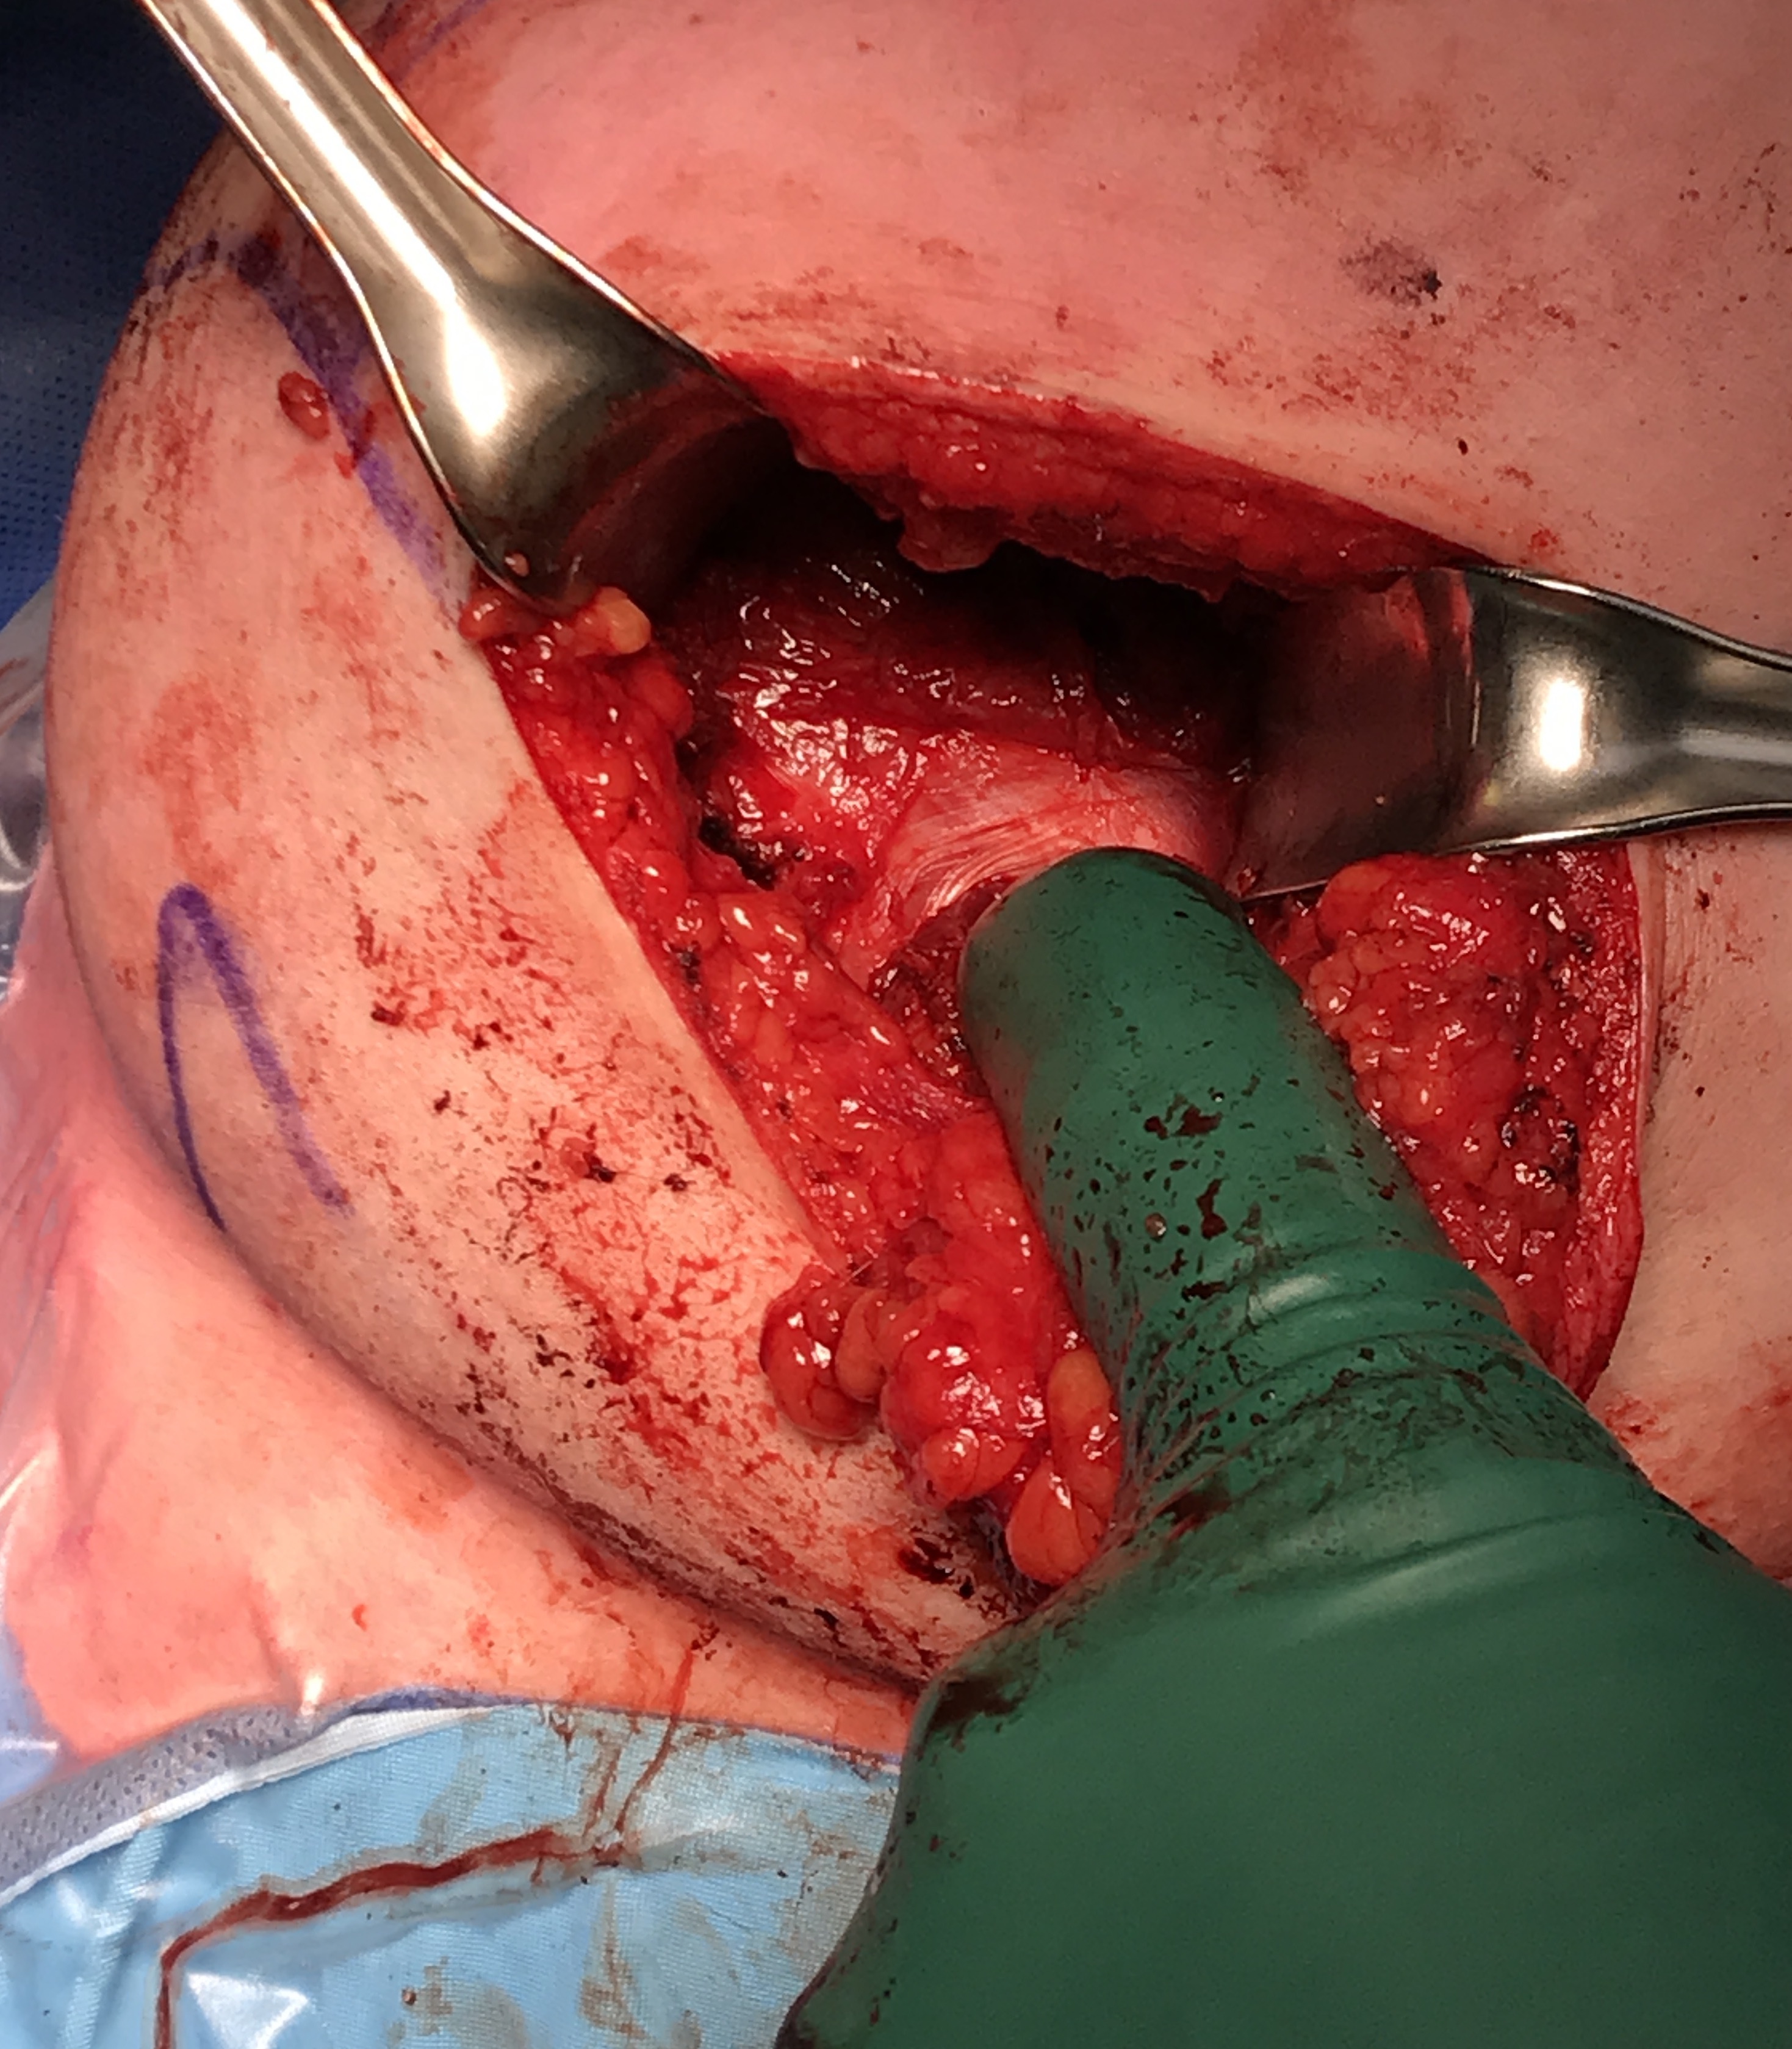

Beach chair or lateral position

- posterior approach / L shaped incision

- elevate or detach deltoid from scapular spine

- detach infraspinatus

Identify and elevate deltoid / detach from scapular spine / identify infraspinatus

Identify interval between infraspinatus and teres minor, detach and reflect infraspinatus to expose posterior capsule and glenoid